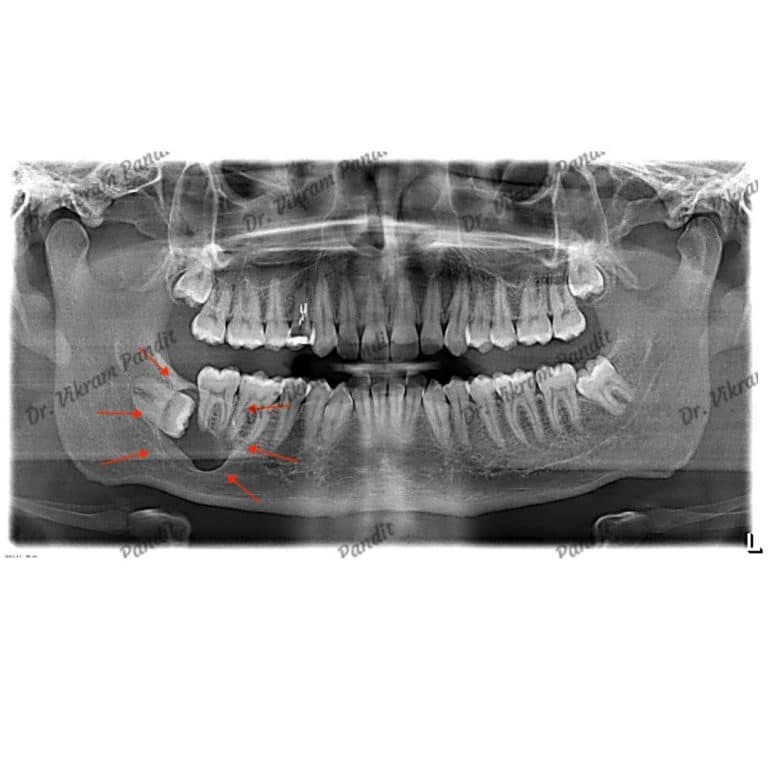

Partially erupted wisdom tooth in a patient's lower jaw. Wisdom teeth

From www.panditclinic.com

Safe Wisdom Teeth Removal Pandit Clinic, Pune Cheek Biting From Erupted Wisdom Teeth Factors increasing cheek bite risk. if the wisdom teeth are partly erupted, it might push into the mouth lining and bite the cheek, producing a wound. wisdom tooth biting your cheek is a common issue caused by the improper eruption or misalignment of the third molars, leading to pain,. Red and swollen gum tissue is called gingivitis. Wisdom. Cheek Biting From Erupted Wisdom Teeth.